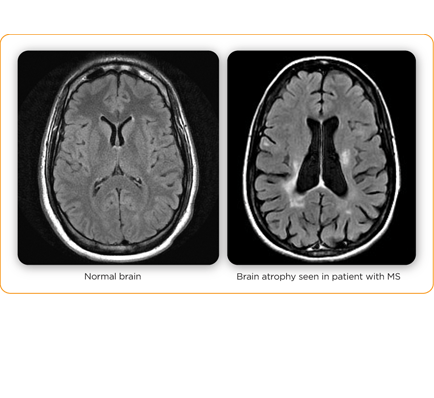

My doctor did a wonderful and thorough job explaining what he looks for in scans, putting everything into layman’s terms, and patiently fielding questions along the way. We saw slides of brains with active lesions, old lesions, and brains with permanent damage. I’ve seen all of this before, some on my own MRIs, so these slides didn’t shake me too much.

But a little later, Dr. Khatri got to a point in his presentation when he brought up a slide of an MRI patient and pointed out atrophy of the brain, likening it to shriveled cauliflower.

You know, this information wasn’t new to me, but for whatever reason today when I saw my doctor point to a picture of a real person’s brain and show us how it was shrinking…I don’t know. It just pumped me full of fear and sadness. I know that wasn’t the intention, by any means, but I had a weak moment and I let it take over.